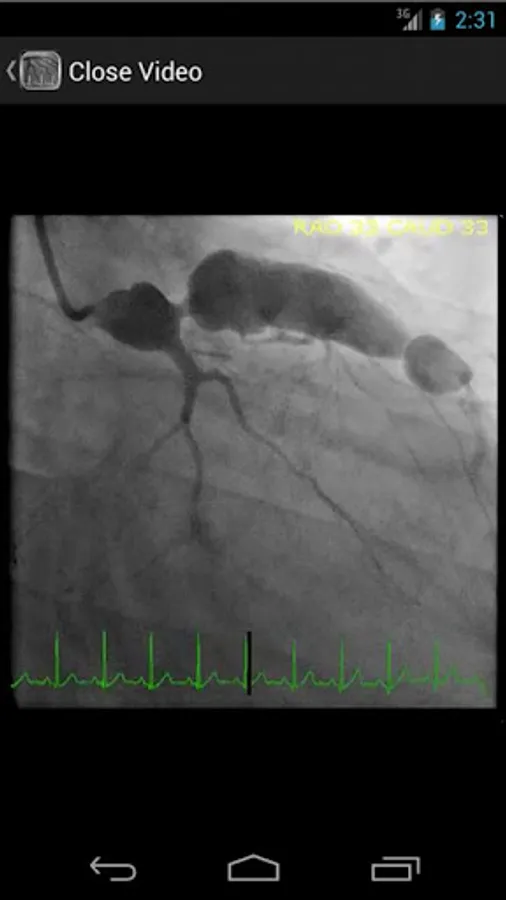

* Searchable database containing more than 30 videos (coronary angiograms, ventriculograms, and aortograms) of both common and rare findings in the cardiac catheterization lab

CathSource provides a detailed overview of important cardiac catheterization and angiography topics, incorporating educational images/videos as well as reviews of pertinent medical literature. CathSource is the ideal application to assist you in understanding and recognizing cardiovascular pathology in the catheterization lab.